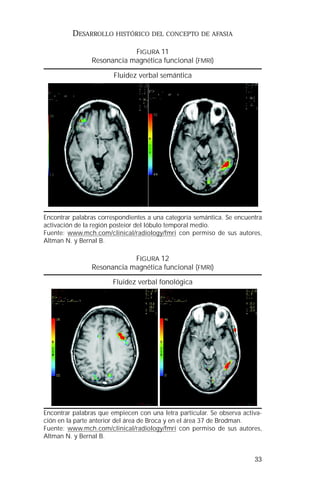

FIGURA 12

Resonancia magnética funcional (FMRI)

Fluidez verbal fonológica

Encontrar palabras que empiecen con una letra particular. Se observa activa-ción

en la parte anterior del área de Broca y en el área 37 de Brodman.

Fuente: www.mch.com/clinical/radiology/fmri con permiso de sus autores,

Altman N. y Bernal B.